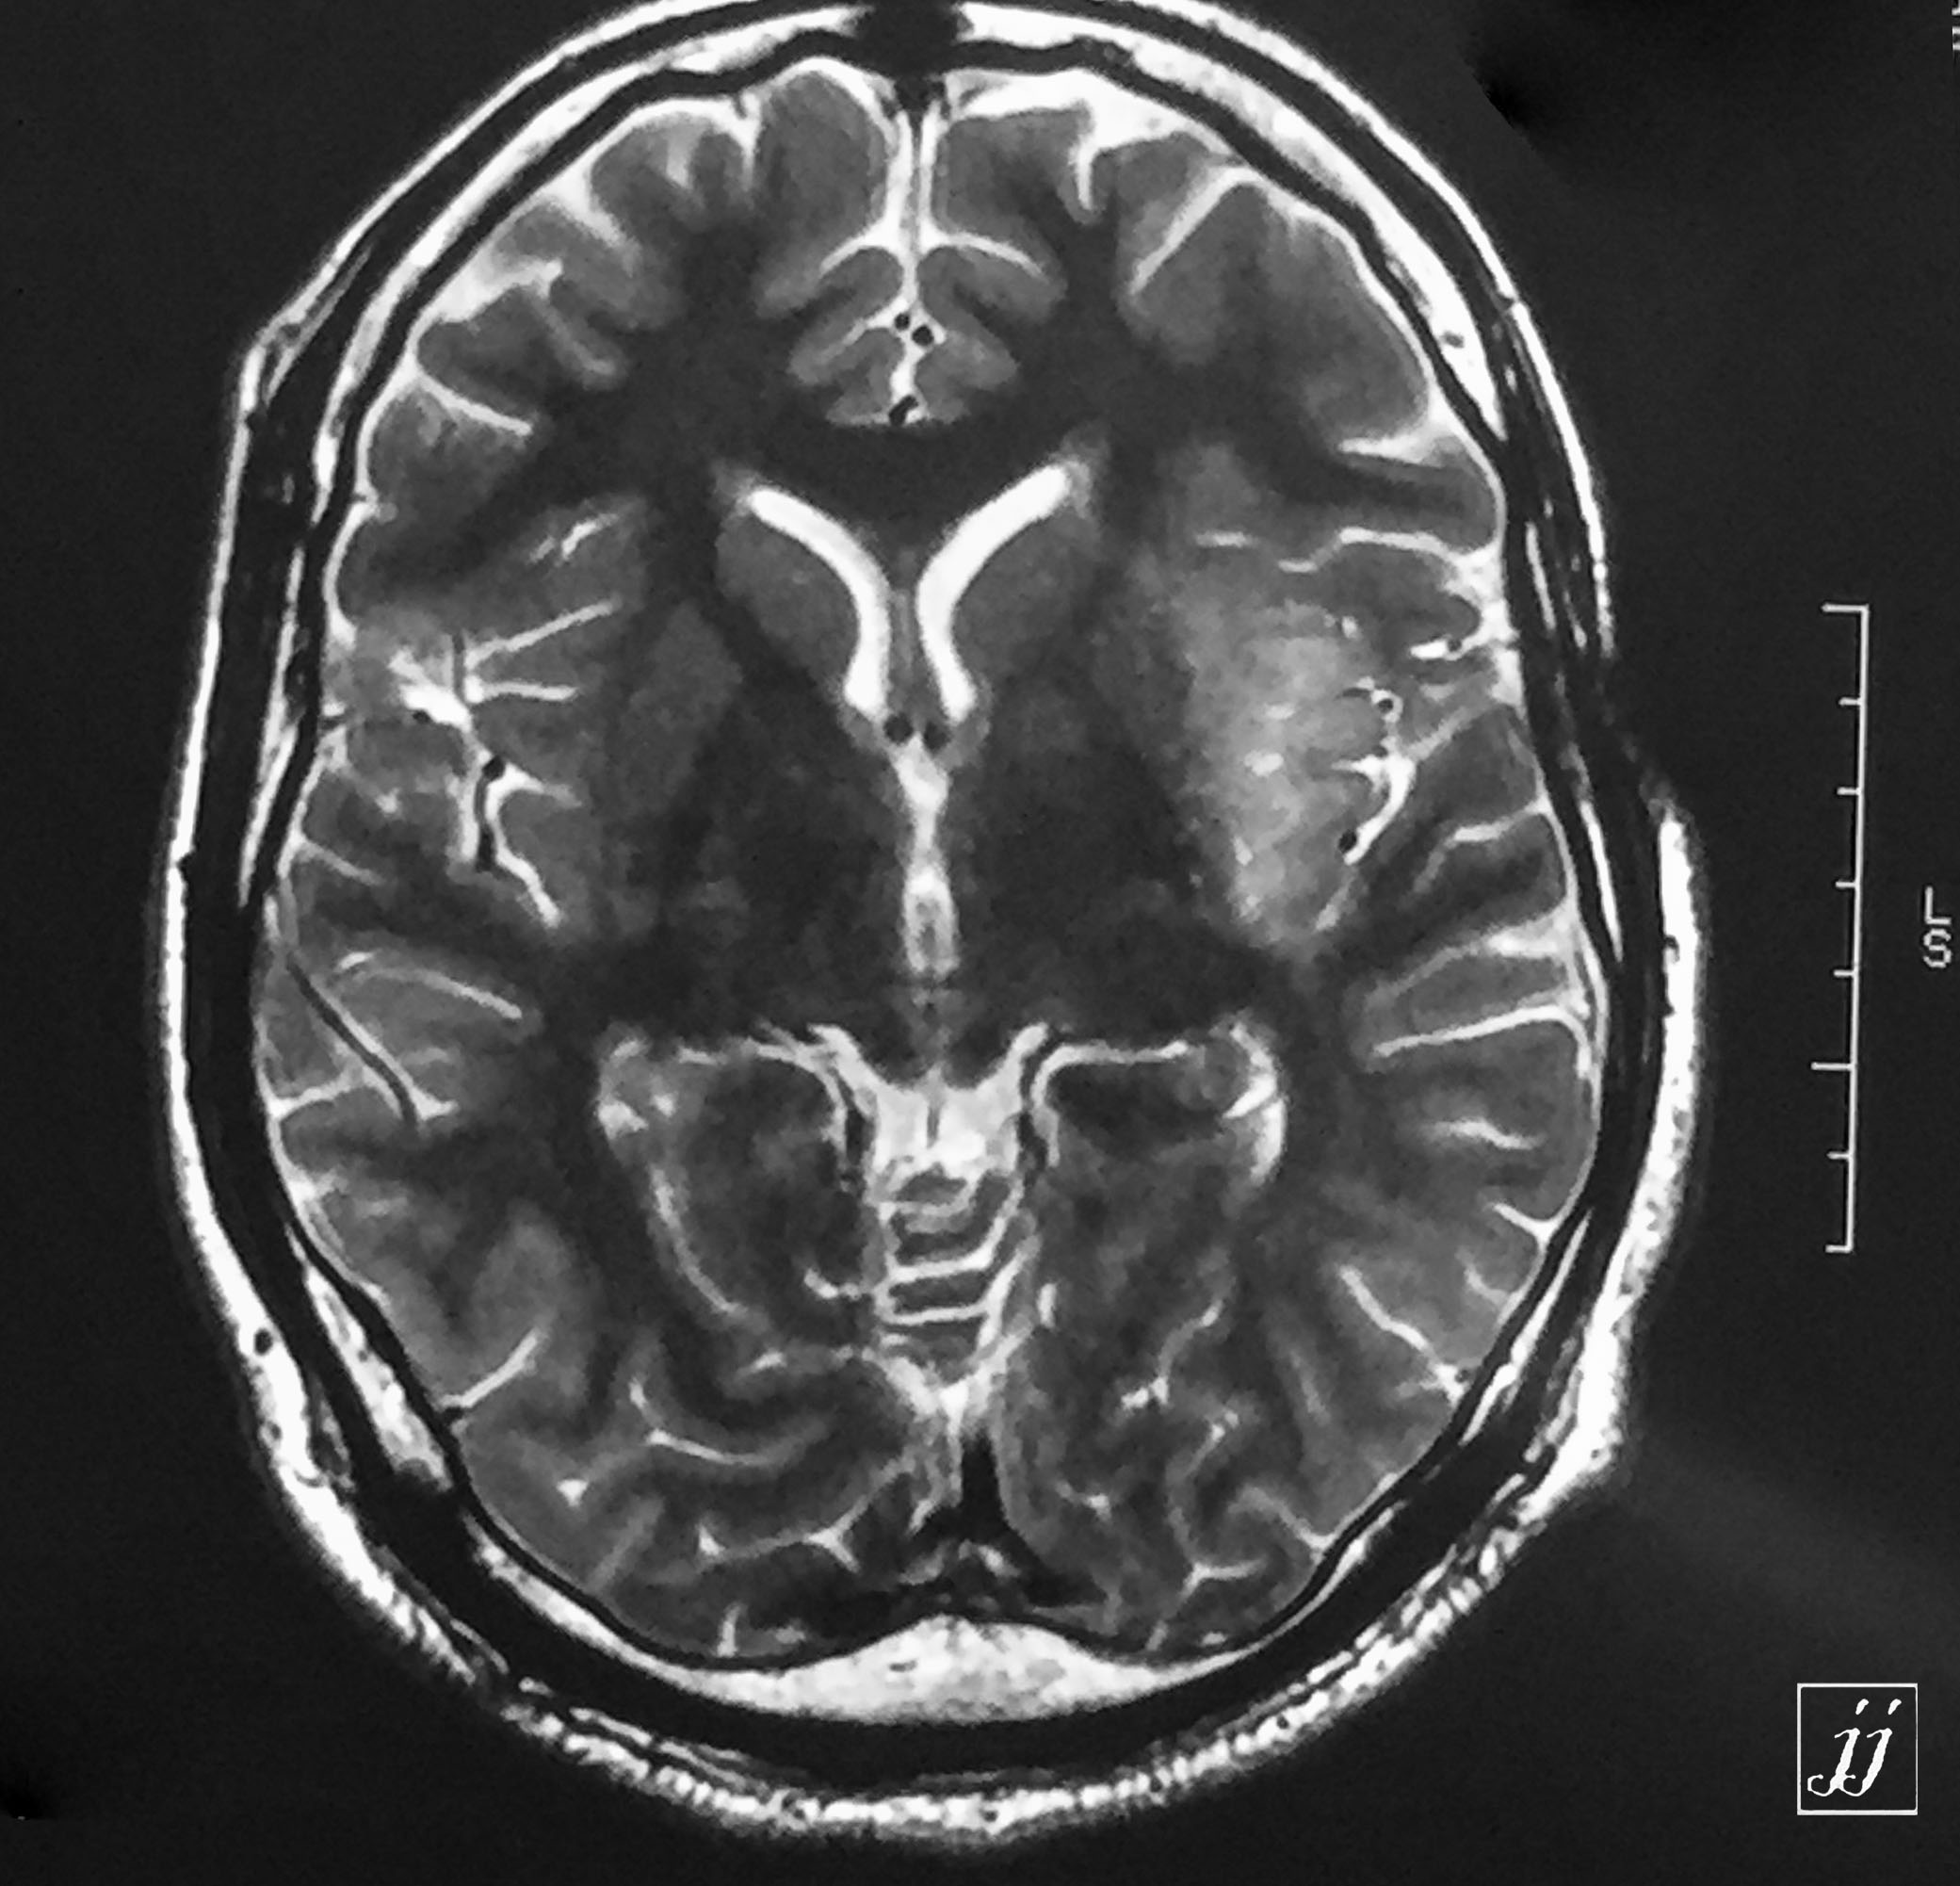

Brain- left side craniectomy and underlying tumor recurrency (infiltrative type) (6)